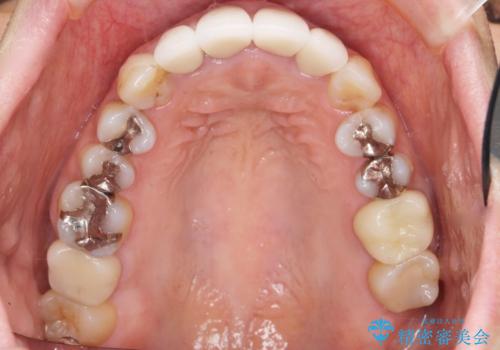

「状態の悪い銀歯がなくなりすっきりした」と喜んで下さいました。

見た目や使用感にご満足頂き、他の部位も現在治療中です。

クラウンの種類:オールセラミッククラウン ベレッツァ